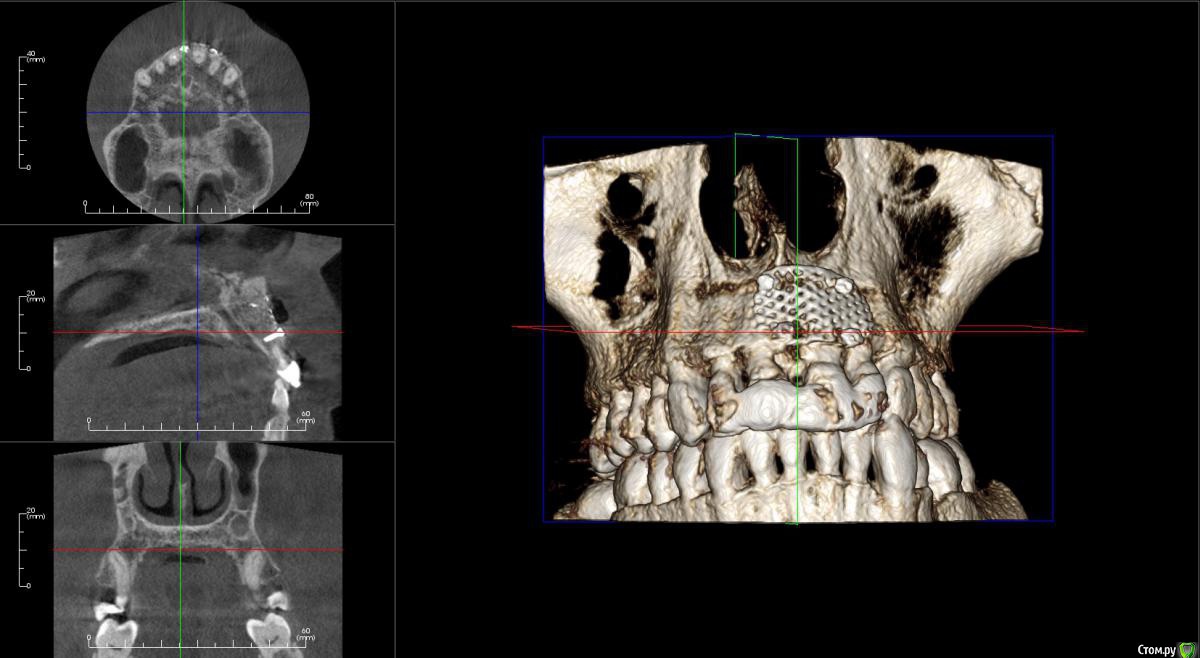

kamranchick Опубликовано 17 апреля, 2016 Поделиться Опубликовано 17 апреля, 2016 Пришел пациентДок привет, что то зуб шатается, можно ли его оставить, вот такие дела)как бы вы поступили бы? Ссылка на комментарий

dantist_movani Опубликовано 27 апреля, 2016 Поделиться Опубликовано 27 апреля, 2016 Пришел пациентДок привет, что то зуб шатается, можно ли его оставить, вот такие дела)как бы вы поступили бы?1)проверил бы на витальность2)Репозиция и шинирование орто ретейнером с жидкотекучим композитомпохожая ситуация была год назад, правда отлом кортикалки не столь значительный был. Ретейнер снял через 6 мес, все Ок, зуб не почернел♿, эод -8 в дуге, пац очень доволен Ссылка на комментарий